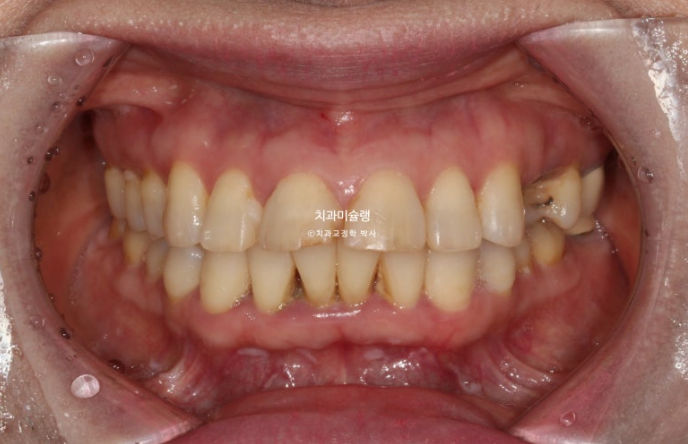

24년 7월 50대 환자분께서 교정치료를 위해 오셨습니다.

앞니가 세로 길이보다 가로길이가 더 긴, 한마디로 납작한 형태입니다.

치아 사이사이 벌어진 틈을 레진으로 메꿔놓고 지내온 것입니다.

충치로 인해 어금니들을 발치하게 되면서 교정치료를 병행하고자 오셨습니다.

일단 앞니 사이사이 레진을 제거해 보았습니다.

아래 앞니 사이 치석도 같이 제거합니다.